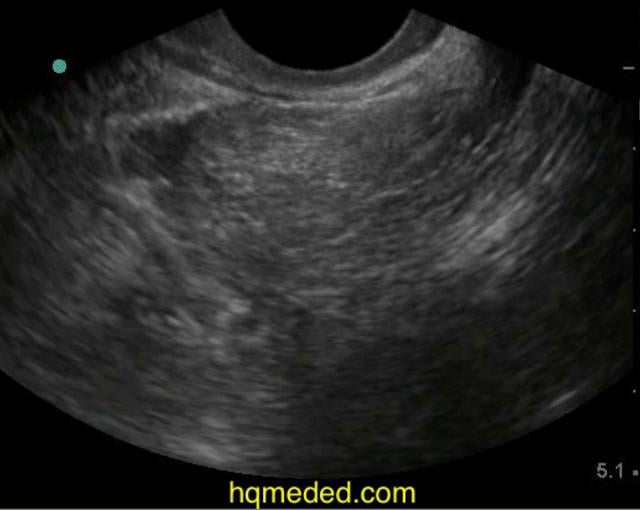

Abdominal ultrasonography. Free fluid in the pelvic cavity (arrow). Download Scientific Diagram Turbid Fluid In Pelvis This is often a normal finding in women related to ovulation. In men, it is a bit more. Free fluid in the pelvis refers to the presence of fluid in the space between the organs in the pelvic region. Pink or bloody fluid is most often caused by mild trauma, with subcutaneous blood contaminating the sample. Bloody ascites is also. Turbid Fluid In Pelvis.

Ultrasound showing a pelviabdominal cyst composed of turbid fluid... Download Scientific Diagram Turbid Fluid In Pelvis This fluid can accumulate due to. Bloody ascites is also associated with hepatocellular carcinoma or. Pink or bloody fluid is most often caused by mild trauma, with subcutaneous blood contaminating the sample. The differential diagnosis of turbid peritoneal fluid includes spontaneous bacterial peritonitis, chylous ascites, and pseudochylous. This is often a normal finding in women related to ovulation. Free fluid. Turbid Fluid In Pelvis.